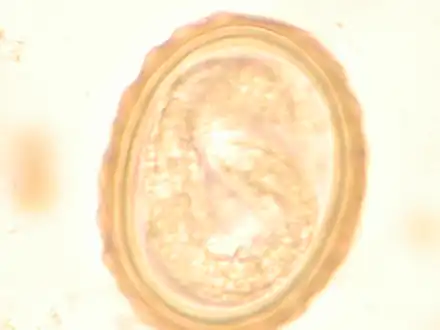

The larva of Ascaris lumbricoides developing in the egg

Ascaris egg, incubation process: The Ascaris egg incubation process consists of placing the egg in a controlled environment, at 26 °C (79 °F) during 28 days, in acidic conditions. This process allows for the evaluation of an egg to determine if it is viable or not.

Most diagnoses are made by identifying the appearance of the worm or eggs in feces. Due to the large quantity of eggs laid, diagnosis can generally be made using only one or two fecal smears.[31] The diagnosis is usually incidental when the host passes a worm in the stool or vomit. The eggs can be seen in a smear of fresh feces examined on a glass slide under a microscope and there are various techniques to concentrate them first or increase their visibility, such as the ether sedimentation method or the Kato technique. The eggs have a characteristic shape: they are oval with a thick, mamillated shell (covered with rounded mounds or lumps), measuring 35–50 micrometer in diameter and 40–70 in length. During pulmonary disease, larvae may be found in fluids aspirated from the lungs. White blood cell counts may demonstrate peripheral eosinophilia; this is common in many parasitic infections and is not specific to ascariasis. On X-ray, 15–35 cm long filling defects, sometimes with whirled appearance (bolus of worms).